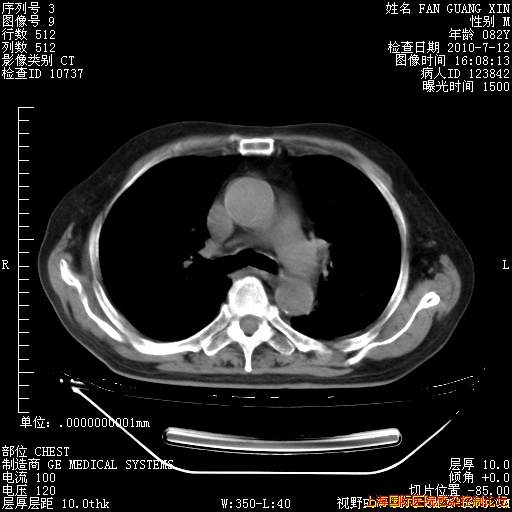

今天复查CT

今天CT

整整相隔30天的肺部CT好像有所好转啊。甲强龙减量第3天,需要观察体温。

海管,自昨日你和我通完话后,不知您岳父消化道症状有无缓解?体温怎样?阅读7.12日胸部ct,个人认为目前激素治疗是有效的,甲强龙减量是适宜的。因在抗痨治疗,需密切观察肝功、肾功能和血常规。不过,老年、长期住院和大量使用激素,很担心菌群失调发生